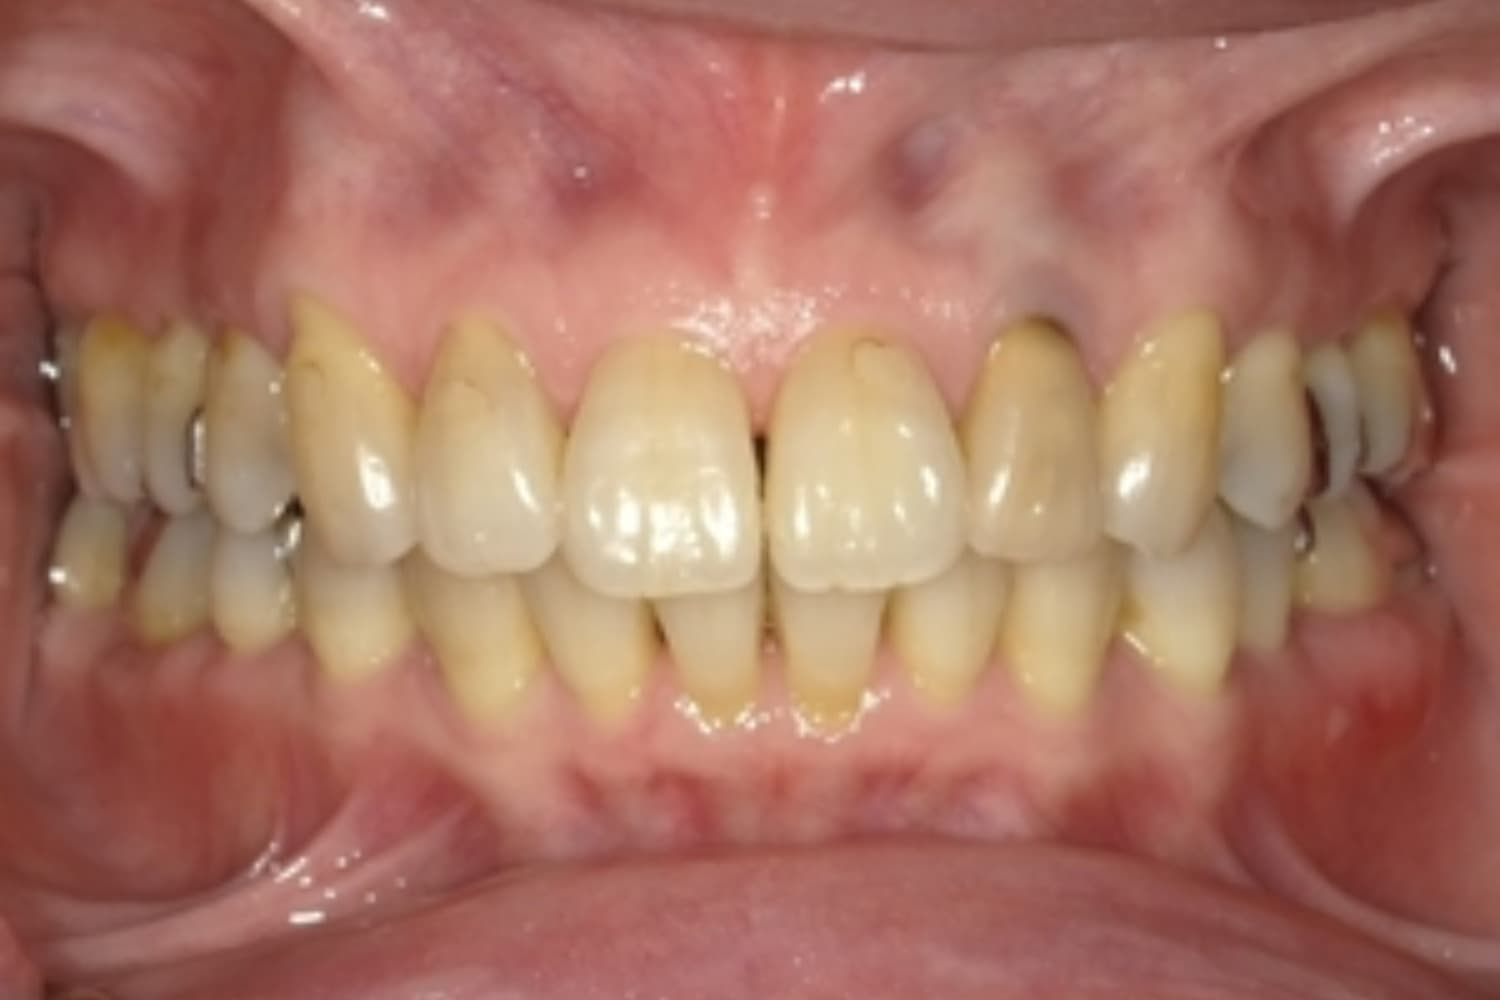

上顎前歯2本欠損症例(2)

Before

After

保存が困難な状態であったため抜歯をおこない、その後インプラントを2本埋入しました。

年齢

67歳

性別

女性

主訴

右上前歯は以前に別の医院で治療中でしたが中断されたため、当院へご相談くださいました。

治療期間

10ヵ月

費用

120万円

副作用・リスク

インプラント治療は外科的な処置を伴い、多少の腫れや痛みが出ることがあります。 多くの場合は鎮痛薬で和らげることができます。